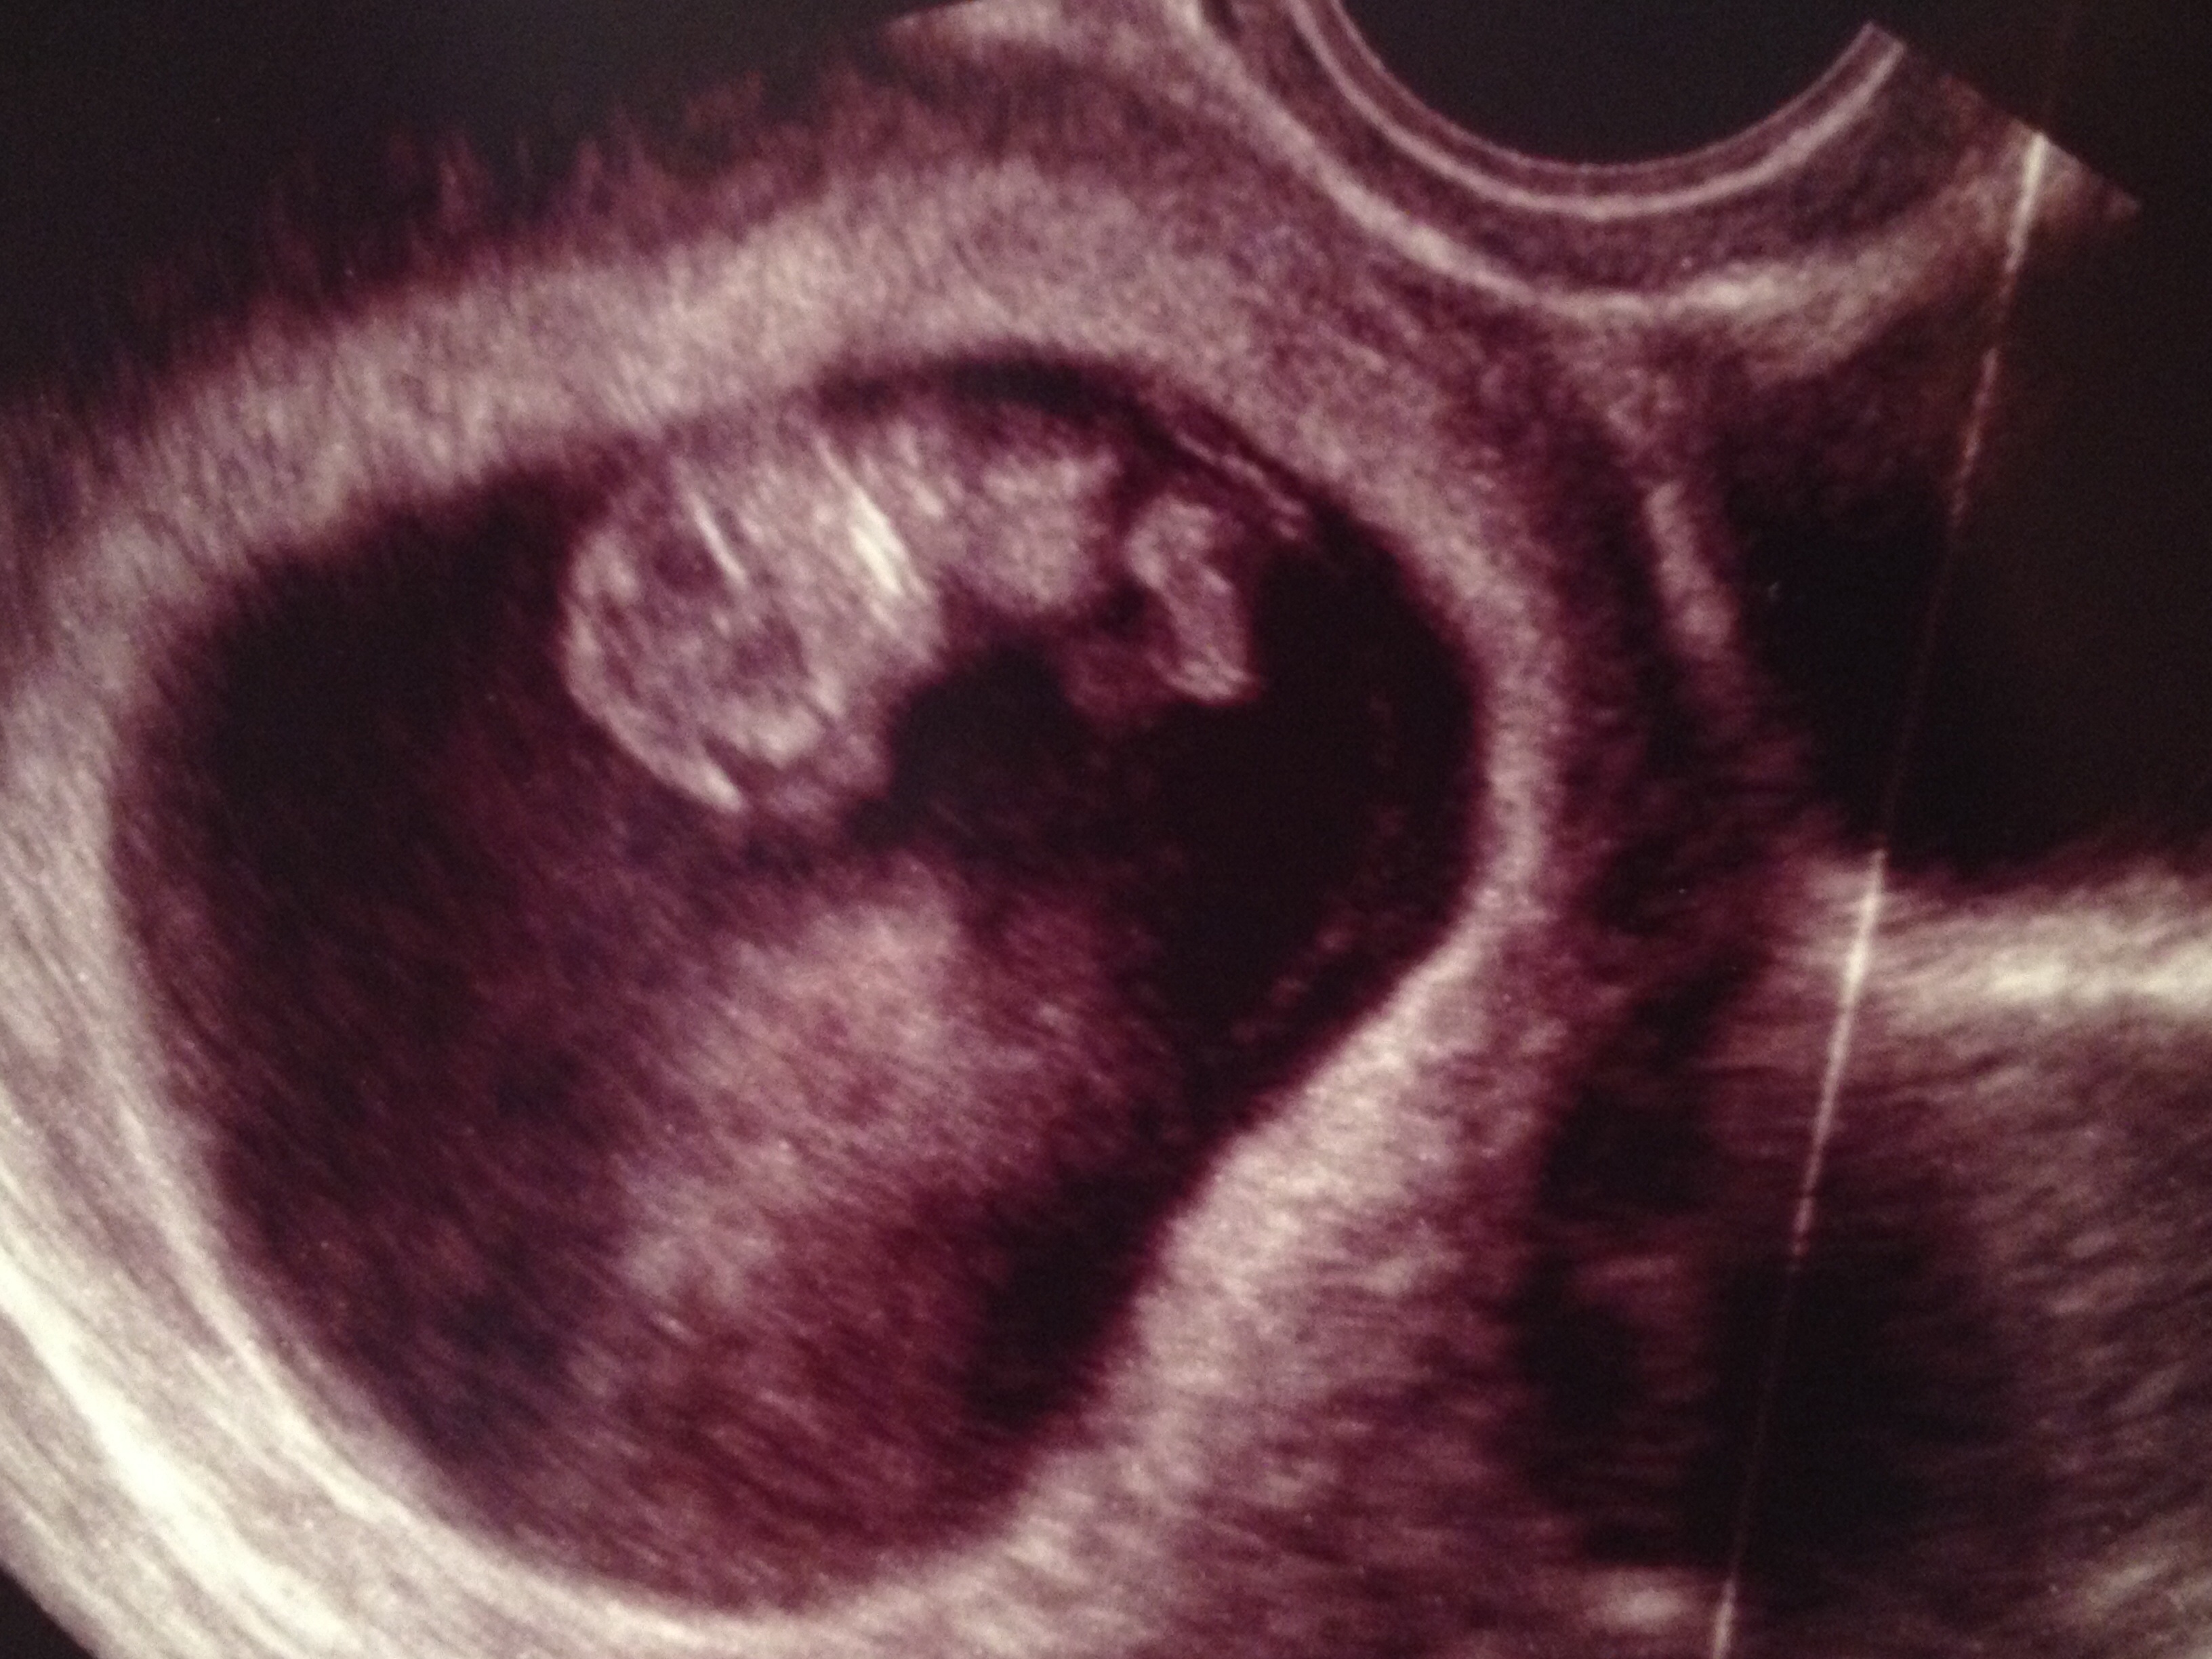

I love u/s pics!! Here is mine from last week @ 8w2d. 167 heartbeat. The tech labeled him/her baby, as you can see...... just in case I wasn't sure what I was looking at! :>

It was such a relief to hear that little heart beating!!